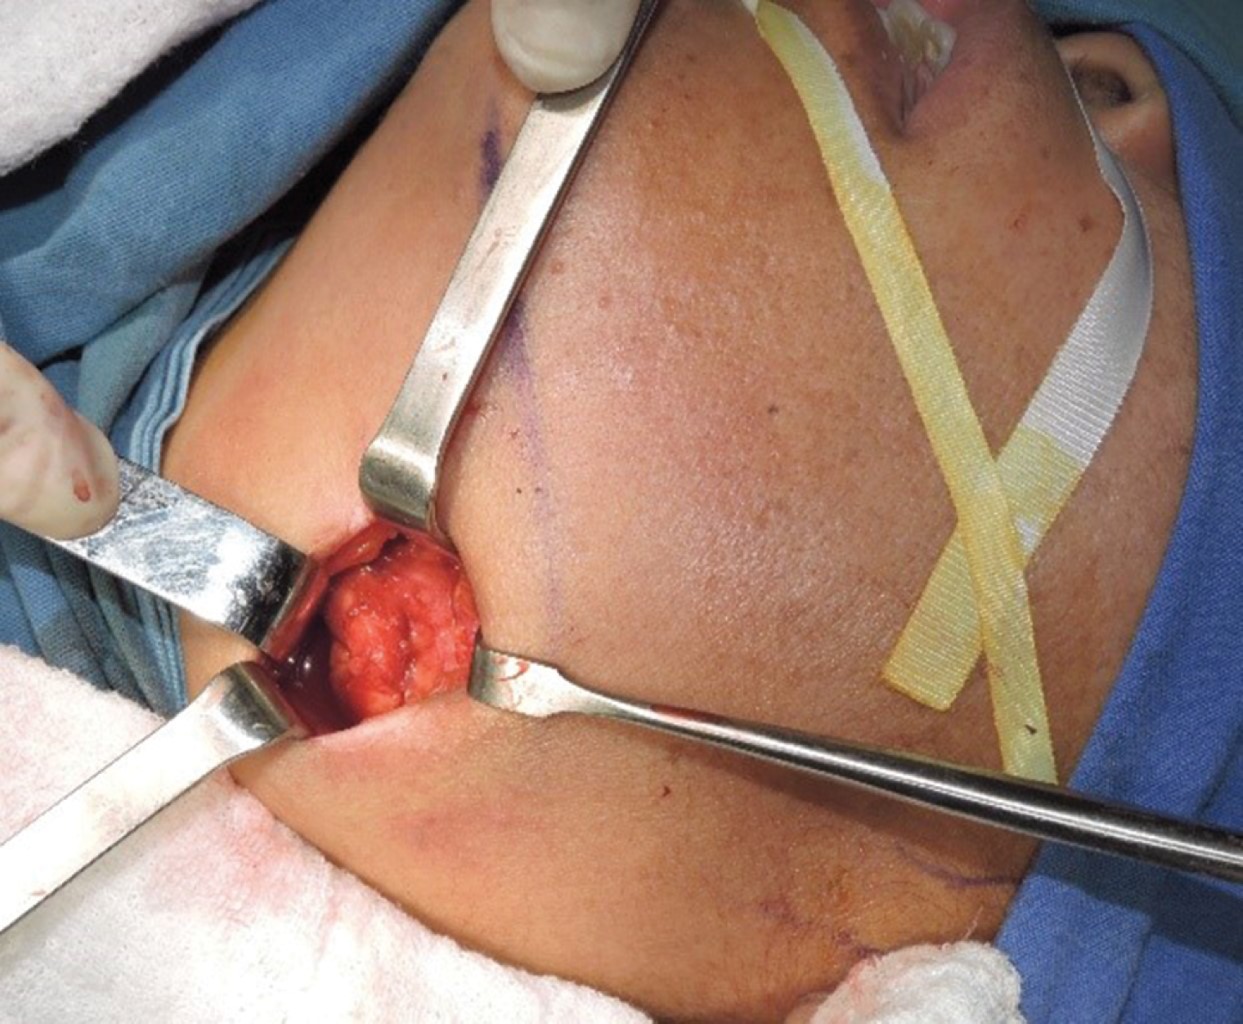

Introduction: Küttner's tumor or chronic sclerosing sialadenitis (CSS) is a rare disease of the major salivary glands. It is characterized by an increase in volume, usually unilateral, although its presence has also been reported in minor salivary glands with or without a relationship with IgG4 disease, producing a fibroinflammatory infiltration in the interlobular septa, but its architecture is preserved and in some cases the presence of stones and positive IgG4 cells. Material and methods: a 44-year-old female patient with tomographic findings of calcification of the left submandibular glands, for which surgical excision of the gland was performed, obtaining a histopathological diagnosis of Küttner's tumor. Results: bimonthly follow-up of the patient continues, currently without the presence of alterations in relation to IgG4 disease. Conclusions: Küttner's tumor or chronic sclerosing sialadenitis (CSS) can sometimes be the initial or only finding of IgG4 disease. The timely diagnosis or the importance of ruling out IgG4 disease is due to all the autoimmune diseases related to it or its possible complications.

Figure 3